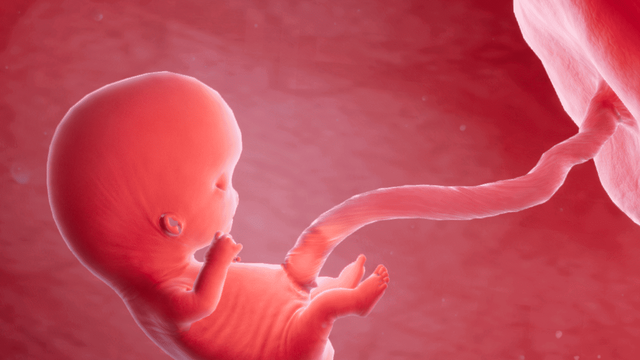

Ho có ảnh hưởng đến thai nhi không là thắc mắc được nhiều mẹ bầu quan tâm khi gặp tình trạng ho trong thai kỳ. Ho thông thường mức độ nhẹ thường không gây ảnh hưởng trực tiếp đến thai nhi, nhưng nếu kéo dài hoặc đi kèm bệnh lý hô hấp thì có thể tác động gián tiếp đến sức khỏe mẹ. Vì vậy, cần đánh giá đúng nguyên nhân và mức độ để có hướng xử lý phù hợp và an toàn.